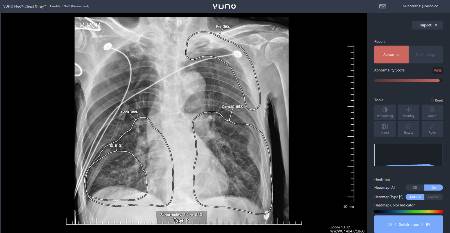

의료 AI 기업 뷰노는 회사의 AI 기반 '뷰노메드 체스트 X 레이'(VUNO Med-Chest X-ray, 이하 Chest X-ray)가 다음달 1일부터 2028년 5월까지 3년간 비급여 사용이 가능해졌다고 15일 밝혔다. 지난 1월 혁신의료기기 통합심사·평가 승인을 받은 데 이어, 이달 보건복지부의 혁신의료기술 관련 고시가 확정된 데 따른 것이다.

뷰노의 Chest X-ray는 흉부 X선 영상을 분석해 5개의 이상 소견(결절, 경화, 간질성 음영, 흉막 삼출, 기흉) 유무를 검출하고 소견 조합을 통해 2개 질환(폐렴, 폐결핵)을 선별하는 진단 보조 소프트웨어다. 만 19세 이상 폐 질환 의심 환자에게 적응증을 획득했다.